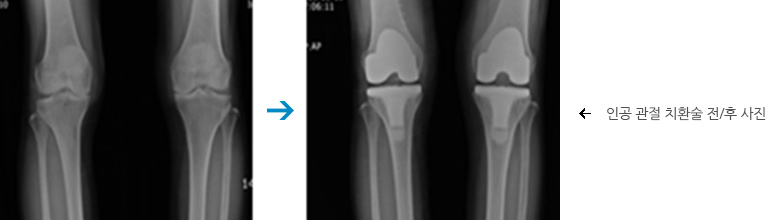

- 무릎 관절염

무릎 관절염